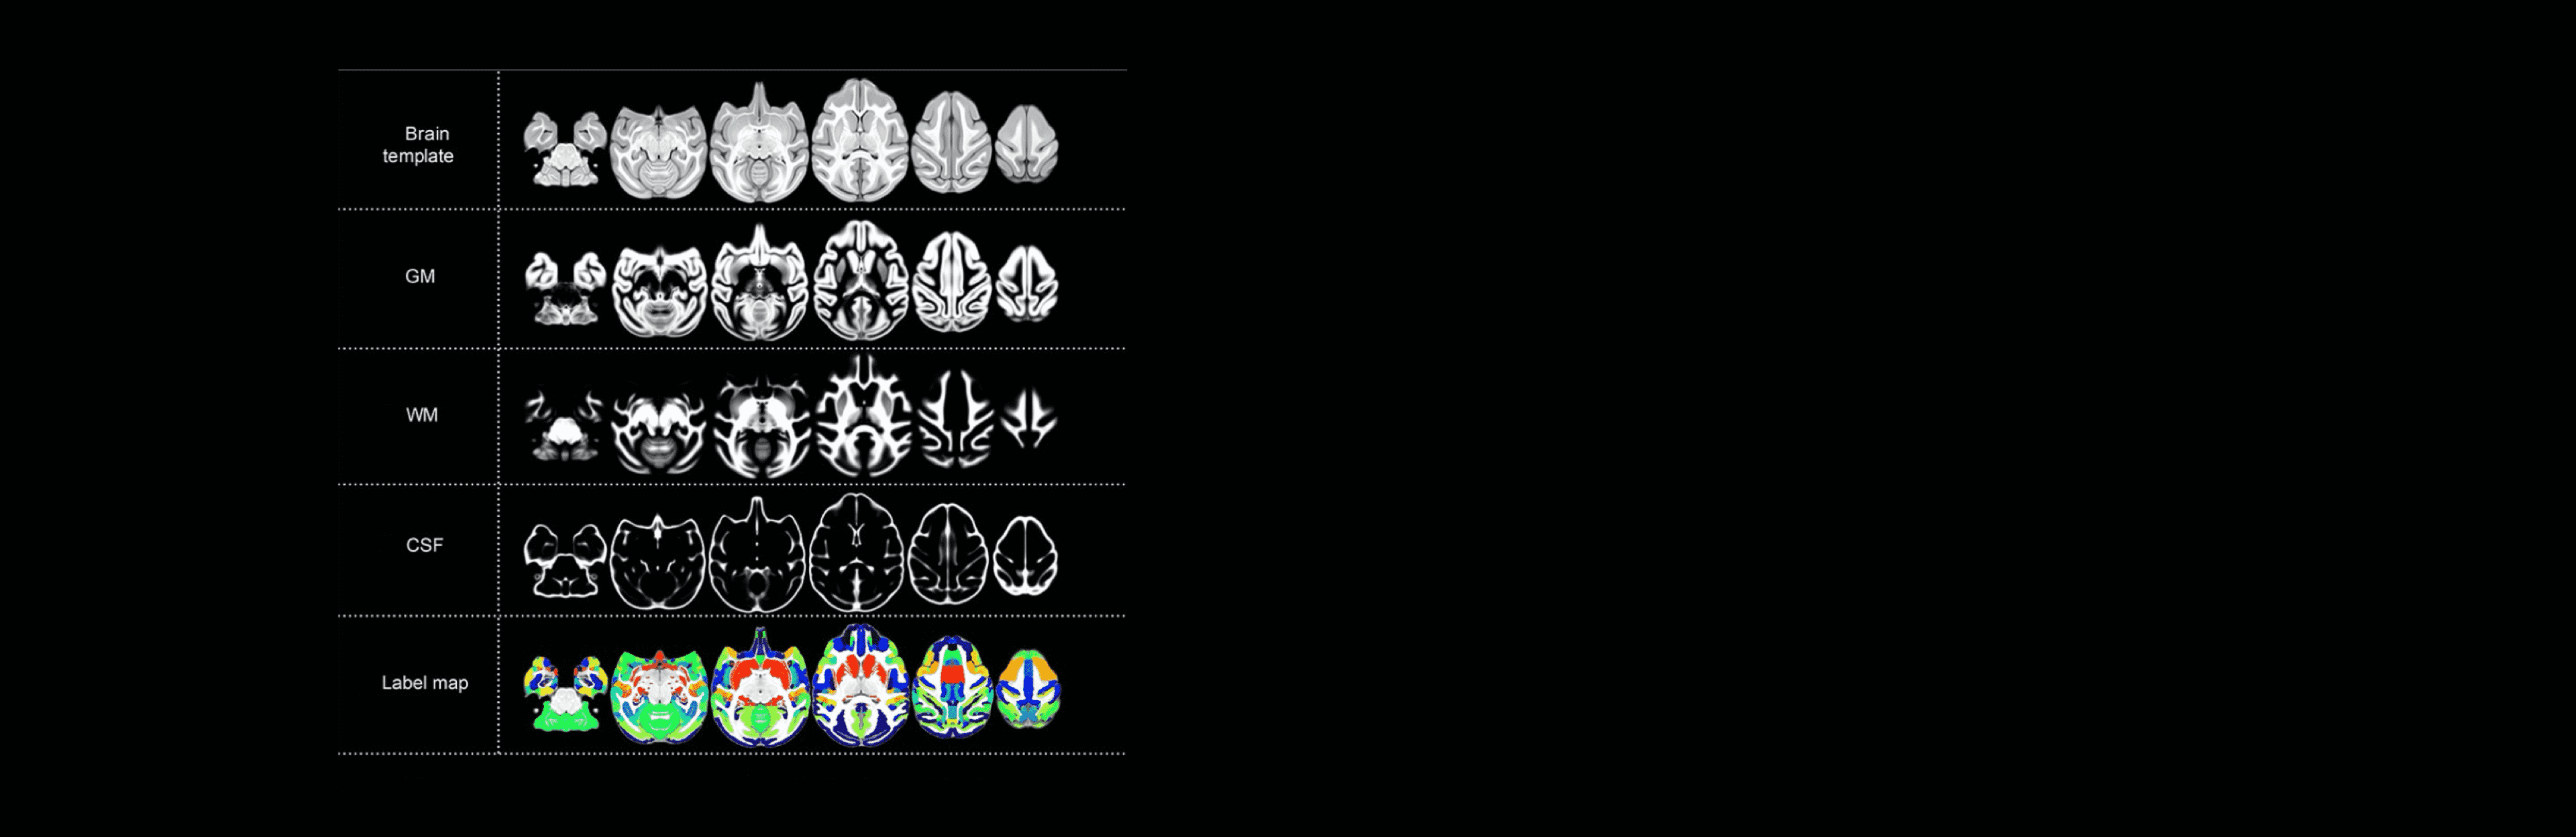

为构建食蟹猴标准化模型,研究人员需要获取大量健康野生型猕猴的磁共振脑影像数据。为此,中国科学院昆明动物研究所和联影医疗合作开发了猕猴头部立体定位仪及12通道专用成像线圈,填补了科研线圈领域空白,能够更好适配猕猴头部结构,极大提升了成像精准度。基于联影医疗高端科研型3.0T磁共振uMR 790等设备,昆明动物所在162只2-9岁的健康食蟹猴上采集了高分辨率的磁共振影像数据,由此制作了食蟹猴脑图谱并建立了标准化模型。

Individual Brain Differences Based on a Population MRI-Based Atlas

参考文献:Lv Q , Yan M , Shen X , et al. NormativeAnalysis of Individual Brain Differences Based on a Population MRI-Based Atlasof Cynomolgus Macaques[J]. Cerebral Cortex, 2020(Suppl 1).